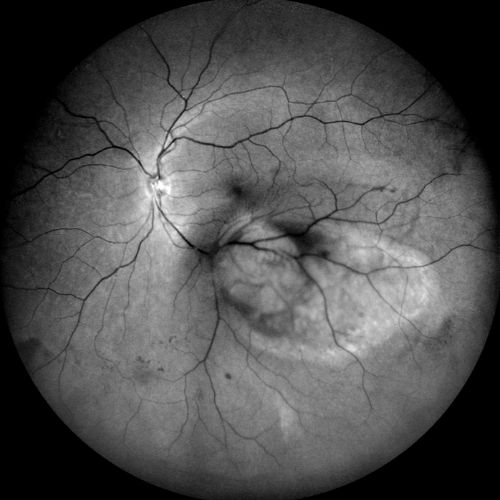

Autofluorescenza

Infrarosso

Fluorangiografia

Fluorangiografie

Retromode

Verde

Rosso